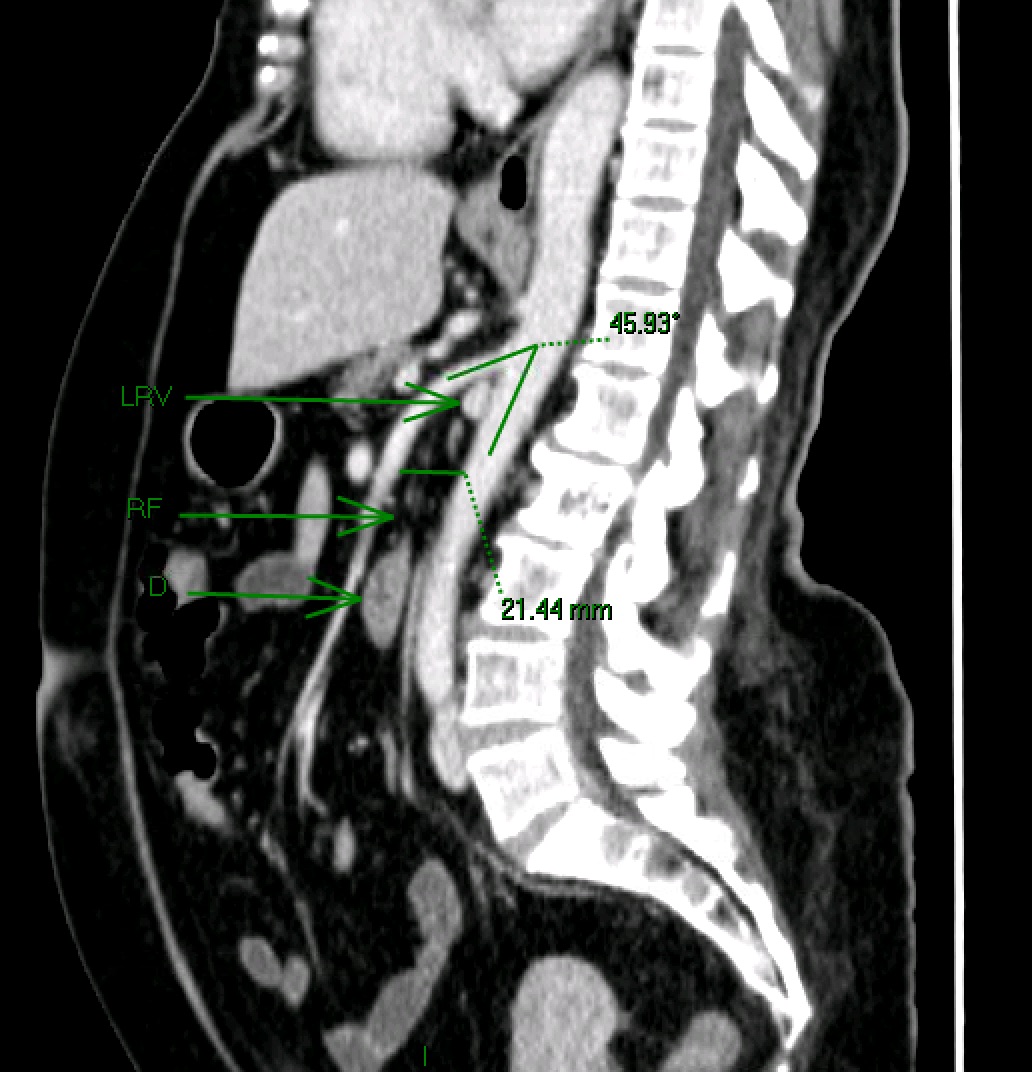

How To Measure Aortomesenteric Angle . On ct, the two key signs of sma syndrome are an aortomesenteric angle of less than 22° and an aortomesenteric distance of less than 8 mm. A to measure the aortomesenteric angle, first obtain a sagittal view of the aorta and delineate landmarks: The former sign has a sensitivity of. Ct scan is helpful in diagnostics in that it allows for measurement of aortomesenteric (ao) angle which aids in confirmation of sma syndrome and has thus replaced mra as. Measure the sma angle as it takes off from the aorta. The narrow angle of the sma is due to lack of fat surrounding the vessel.

The former sign has a sensitivity of. A to measure the aortomesenteric angle, first obtain a sagittal view of the aorta and delineate landmarks: On ct, the two key signs of sma syndrome are an aortomesenteric angle of less than 22° and an aortomesenteric distance of less than 8 mm. The narrow angle of the sma is due to lack of fat surrounding the vessel. Ct scan is helpful in diagnostics in that it allows for measurement of aortomesenteric (ao) angle which aids in confirmation of sma syndrome and has thus replaced mra as. Measure the sma angle as it takes off from the aorta.

Sagittal CT image demonstrating the aortomesenteric angle. Download How To Measure Aortomesenteric Angle Measure the sma angle as it takes off from the aorta. A to measure the aortomesenteric angle, first obtain a sagittal view of the aorta and delineate landmarks: The former sign has a sensitivity of. On ct, the two key signs of sma syndrome are an aortomesenteric angle of less than 22° and an aortomesenteric distance of less than 8. How To Measure Aortomesenteric Angle.